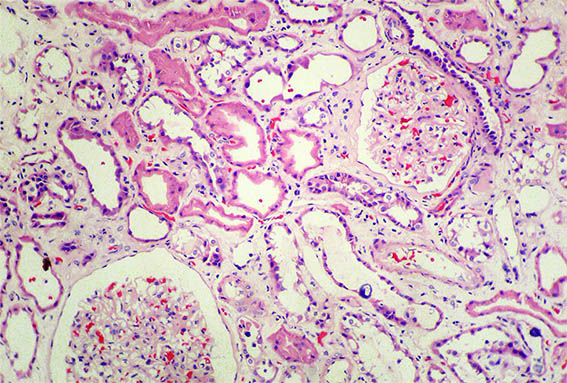

Figura 1. H&E, X100. Note el compromiso tubulointersticial.